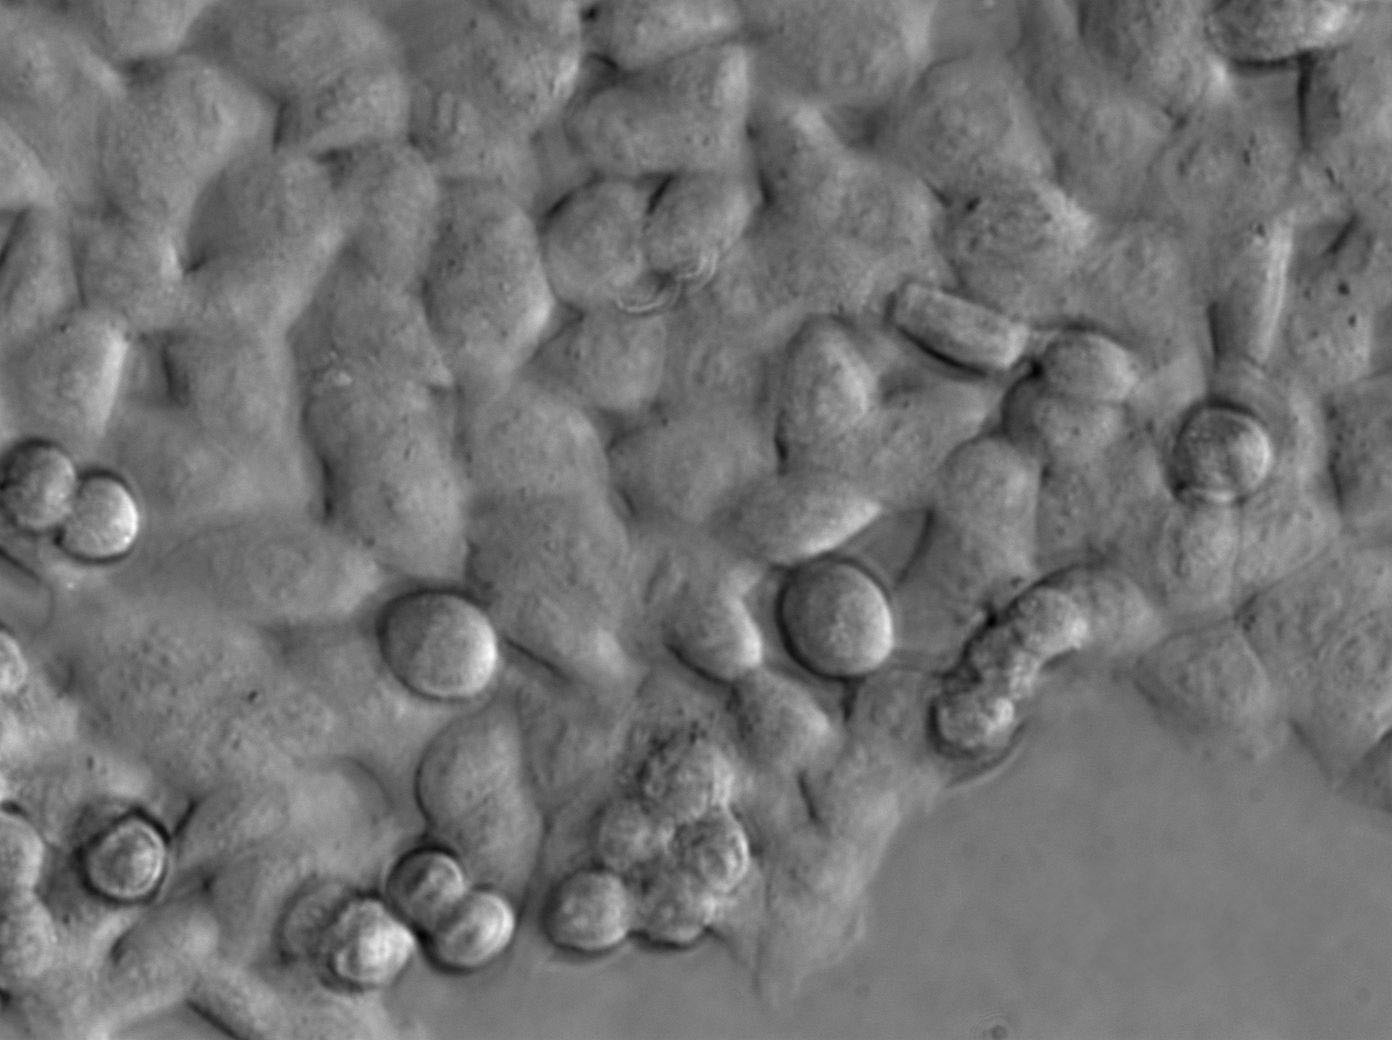

细胞形态:上皮细胞样

细胞生长:贴壁

细胞背景资料:肝癌;男性

细胞传代方法:1:2-1:3传代;每周换液2-3次。

细胞生长特性:贴壁